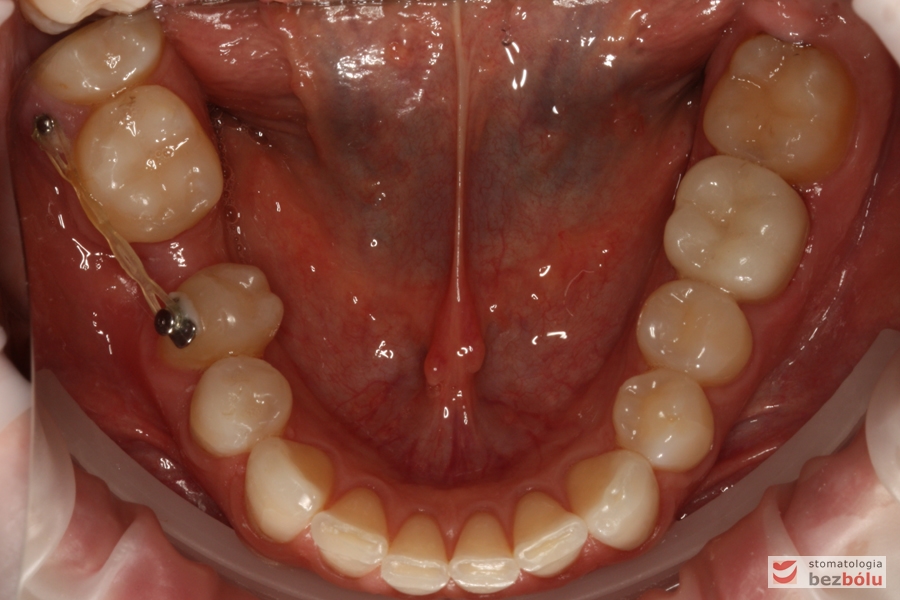

Żuchwa - widok okluzyjny, wprowadzana piątka do łuku za pomocą mikrośruby

Żuchwa – widok okluzyjny, wprowadzana piątka do łuku za pomocą mikrośruby